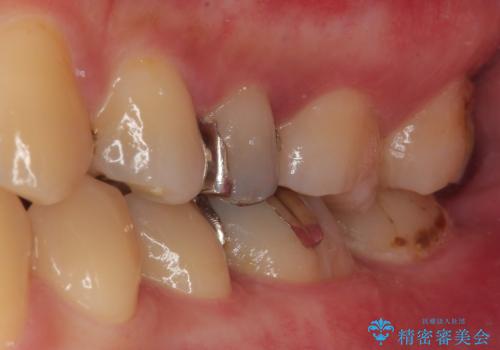

- 銀歯が何度も外れるとのことで来院された患者様です。

保険の金属の詰め物(メタルインレー)が適合性が悪い状態で入っていたので、詰め物も大きかったのでオールセラミッククラウンでの治療をご提案しました。

拡大鏡視野下で、金属の詰め物(メタルインレー)、虫歯の除去を行い、オールセラミッククラウンに適した形に整えました。